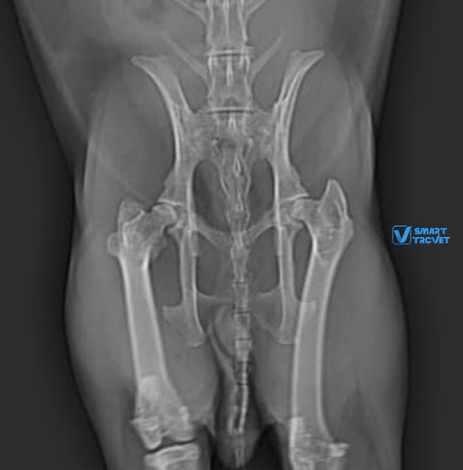

Lili, a two-year-old female rabbit, fell from her owner’s arms, resulting in lameness of the right leg. Radiographs of the pelvis and right hindlimb (excluding the area from mid-tibia to foot) were prepared and found to be of good quality. The radiographs revealed a complete luxation of the right coxofemoral joint, with a dorso-cranial displacement. Both acetabula and the left hip appeared normal. Hip dysplasia was not present. All other bones and joints of the hind limbs were normal, with no additional radiographic abnormalities identified. The final diagnosis, based on the radiographic findings, was traumatic dorso-cranial luxation of the right hip joint.